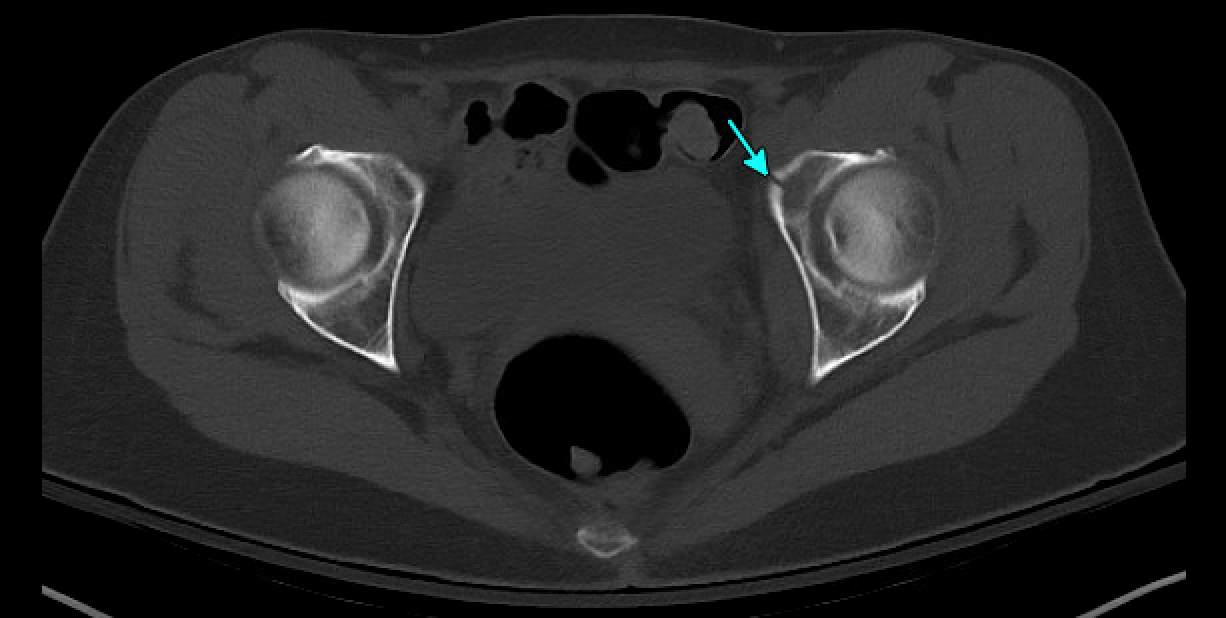

CT later confirmed fractures involving the left acetabulum and ilium, and bilateral pubic rami.